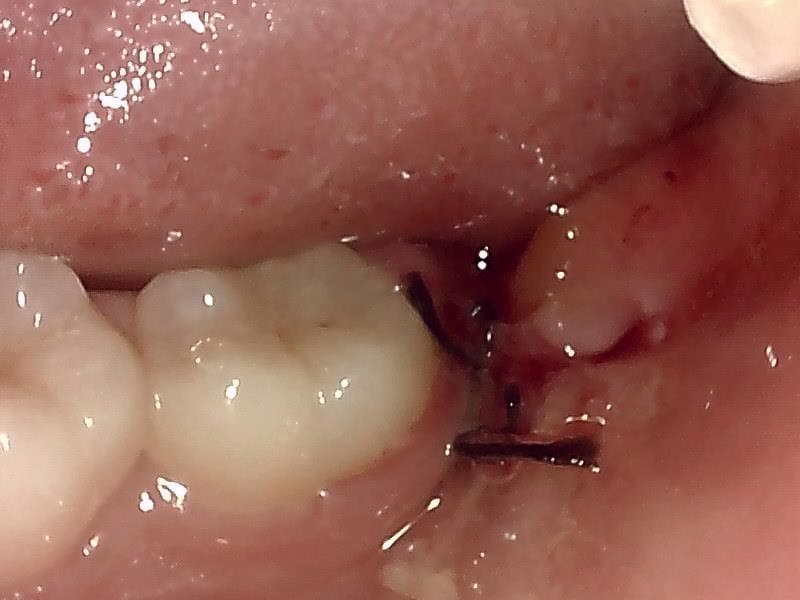

抜歯窩の写真 (左上)

止血シーネで止血処置をする。(左上)

当院では、傷口は最小限に、骨は極力削らずに行います。

骨が歯を覆っているケース以外は骨を削ることはありません。

親知らずのみにアプローチし歯を分割し最小限の傷口で取り出します。

歯肉を切開し、歯が見えるようにして、

周辺の骨を削らないように親知らずを分割し抜きやすくしていきます。

この抜歯法により術後の腫れ痛みが大幅に軽減されます。